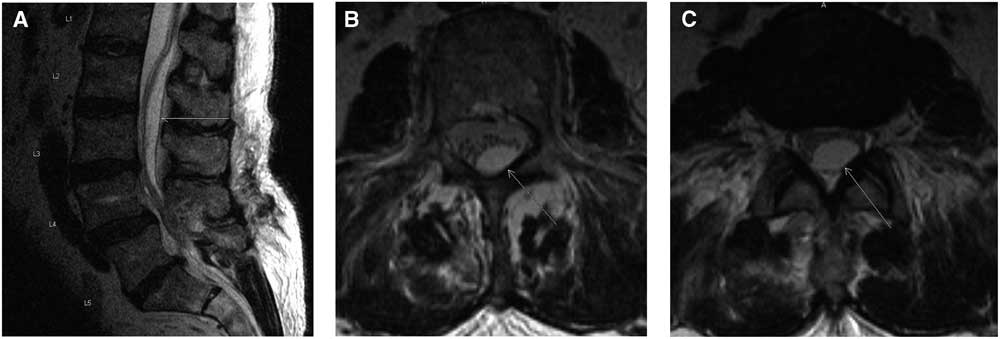

On postoperative day 1, the patient complained of increasing lower limb weakness with grade 2 of 5 strength in all lumbar nerve root distributions along with decreased sensation. Urgent magnetic resonance imaging (MRI) scans of the total spine revealed postoperative changes including an epidural hematoma causing severe central canal stenosis at L4-L5 and a superiorly located intradural collection causing severe displacement and compression of the adjacent nerve roots (L1-L5) (Figure 3A-C). There was heterogeneous T1 and T2 signal at the L4-L5 level in keeping with an extradural hematoma. A separate collection with high T2 and low-to-isointense T1 signal that extended superiorly to the L1 level represented an arachnoid cyst and intradural hematoma on imaging. This was classified as intradural because epidural fatty tissue was present without displacement of the dura mater.

Figure 3 Immediate postoperative T2-weighted mid-sagittal (A), axial at L2 (B), and axial at L2-L3 (C) MRI scans. The arrow shows the intradural cyst with displacement of the cauda equina nerve roots anteriorly within the dural sac.